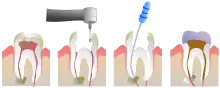

Le traitement endodontique consiste à :

- éliminer ce qui reste de tissus vivants infectés ou potentiellement infectés à l'intérieur de la dent (pulpe dentaire)

- bien nettoyer l'intérieur de cette dent, par une action mécanique : grattage de la surface intérieure des canaux pulpaires (à l'aide de limes endodontiques manuelles ou mécaniques), associée à une action chimique : irrigation avec de l'hypochlorite de sodium (eau de Javel diluée à 3 %), qui est le désinfectant le plus efficace.

- mettre en forme la lumière canalaire jusqu'au foramen apical, à l'aide de limes manuelles ou de limes mécanisées afin que la solution d'irrigation pénètre partout.

- sécher le système canalaire

- réaliser l'obturation canalaire, le plus souvent à l'aide de gutta-percha chauffée ou froide, liée aux parois dentinaires avec un ciment canalaire (le plus souvent un mélange d'oxyde de zinc et d'idothymol, appelé pâtes de Roy).

Pour cela le dentiste réalise généralement une anesthésie locale, pour que le geste ne soit pas douloureux (la dent, même partiellement nécrosée, restant généralement sensible). Une ouverture adéquate est réalisée au niveau de la face occlusale de la dent, pour accéder à la pulpe camérale et radiculaire.

Ensuite il faudra reconstituer la dent, soit avec une obturation coronaire si cette dent n'est pas trop délabrée, soit par une reconstitution prothétique (couronne) si elle est trop délabrée, afin d'assurer l'étanchéité du traitement et éviter que la racine ne soit recolonisée par les bactéries.